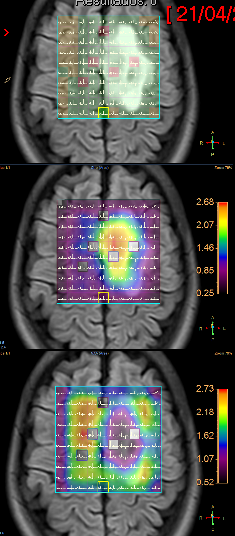

Fig3a,b – Espectroscopia de Múltiplos Voxels (EMV) em caso de glioma de alto grau (Astrocitoma anaplásico – III) frontal esquerdo. Traçados de mini voxels colocados no interior e no tecido cerebral vizinho (a, b), para avaliar grau de invasividade tumoral mostram níveis elevados de cholina dentro e fora da lesão.

Fig3c,d – Espectroscopia de Múltiplos Voxels (EMV) em caso de glioma de alto grau (Astrocitoma anaplásico – III) frontal para sagital esquerdo. Traçados de mini voxels colocados no interior e no tecido cerebral vizinho para avaliar grau de invasividade tumoral mostram níveis elevados de cholina dentro e fora da lesão redução do NAA (c) e acúmulo de lactato(d).

A figura acima apresenta mapa de metabólitos (cholina e NAA) que mostram redução de NAA por substituição de tecido normal por células neoplásicas e acúmulo de cholina por proliferação celular glial (c). Também o mapa de metabólitos (cholina e lactato), mostra, além de acúmulo de cholina, a presença de lactato, inferindo hipóxia intratumoral (d).